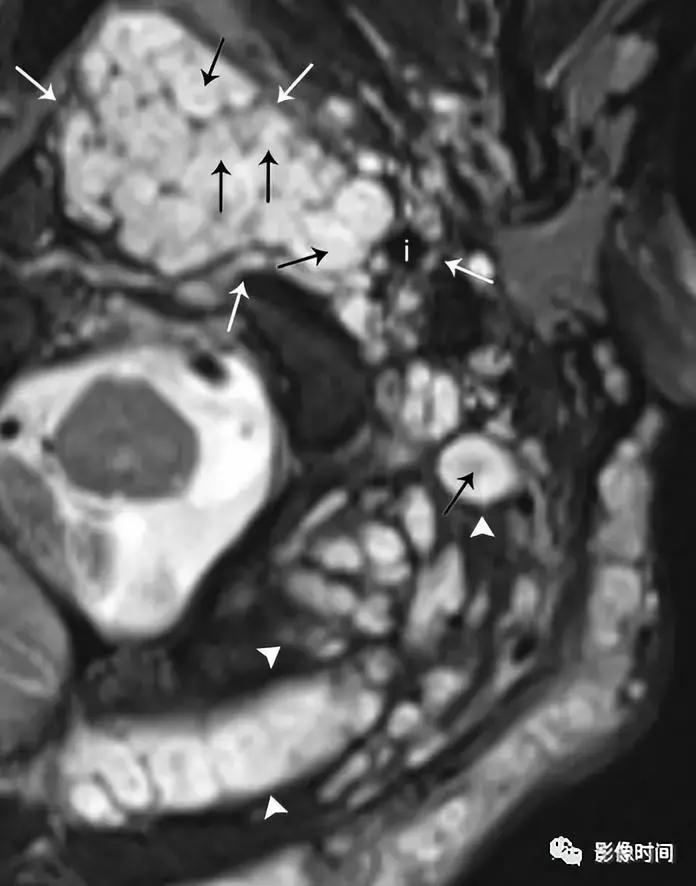

(1).颈动脉体瘤:约占颈部副节瘤的 60%,45-60 岁多见,无明显性别差异。多位于颈总动脉分叉处内侧,往往生长缓慢和无痛,由于病灶靠近 10-12 颅神经,因此患者可以出现吞咽困难、声音嘶哑等。

模式图显示颈动脉体瘤富含血管,并导致颈内动脉及颈外动脉距离增宽,包绕颅神经。增强 CT 显示右侧动脉间隙中心的边界清晰肿块,导致颈内动脉 (i) 和颈外动脉 (e) 分离。颈内静脉向外后移位(j)。左颈动脉间隙 (虚线圆) 显示颈动脉与颈内静脉的正常关系。T2WI 显示边界清晰的信号肿块 (白色箭头),多个内部流动信号 (黑色箭头)。DSA 显示颈动脉分叉处有富血管团块 (箭头)。